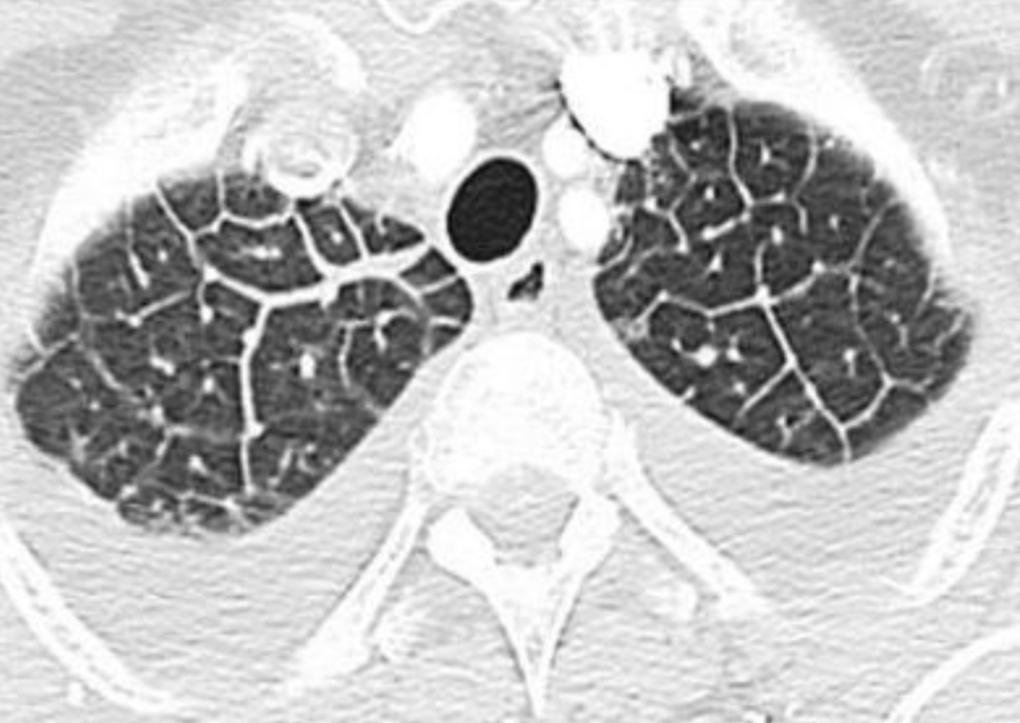

def: Es una estructura anatómica que se ve en la tomografía, divido en septos interlobulillares

A

lobulillo pulmonar secundario

Este patron pulmonar ocurre por ocupación o enfermedad del intersticio, dando una forma de “red” o “telaraña” con pequeños puntos en el centro

patrón intersticial/reticular

¿Cómo se ve el patrón intersticial/reticular en TC y RX?

RX: líneas finas o gruesas que se ven en los extremos del pulmón

TC: Líneas finas o gruesas